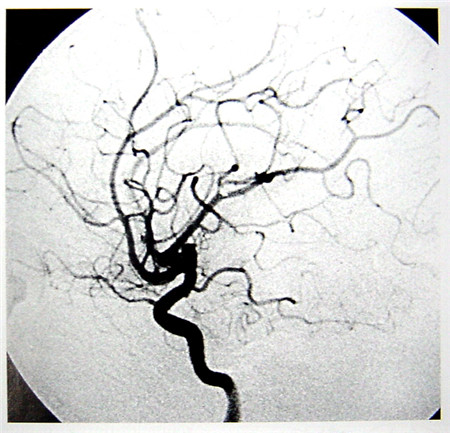

數(shù)字減影血管造影(DSA)簡(jiǎn)介

數(shù)字減影血管造影技術(shù)(Digital Subtraction Angiography,DSA)是一種新的X線成像系統(tǒng),是常規(guī)血管造影術(shù)和電子計(jì)算機(jī)圖像處理技術(shù)相結(jié)合的產(chǎn)物。DSA的成像基本原理是將受檢部位沒(méi)有注入造影劑和注入造影劑后的血管造影X線熒光圖像,分別經(jīng)影像增強(qiáng)器增益后,再用高分辨率的電視攝像管掃描,將圖像分割成許多的小方格,做成矩陣化,形成由小方格中的像素所組成的視頻圖像,經(jīng)對(duì)數(shù)增幅和模/數(shù)轉(zhuǎn)換為不同數(shù)值的數(shù)字,形成數(shù)字圖像并分別存儲(chǔ)起來(lái),然后輸入電子計(jì)算機(jī)處理并將兩幅圖像的數(shù)字信息相減,獲得的不同數(shù)值的差值信號(hào),再經(jīng)對(duì)比度增強(qiáng)和數(shù)/模轉(zhuǎn)換成普通的模擬信號(hào),獲得了去除骨骼、肌肉和其它軟組織,只留下單純血管影像的減影圖像,通過(guò)顯示器顯示出來(lái)。通過(guò)DSA處理的圖像,使血管的影像更為清晰,在進(jìn)行介入手術(shù)時(shí)更為安全。

數(shù)字減影血管造影DSA腦血管圖像顯示 核磁共振MRI掃描腦組織圖像